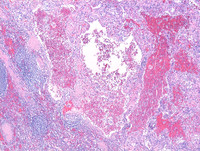

Figure 1: H&E images

Low power photomicrographs reveal a well demarcated tumor within the red pulp and uninvolved spleen at the periphery. Tumor shows proliferation of anastomosing vascular channels interspersed with dilated vascular and cyst like spaces.